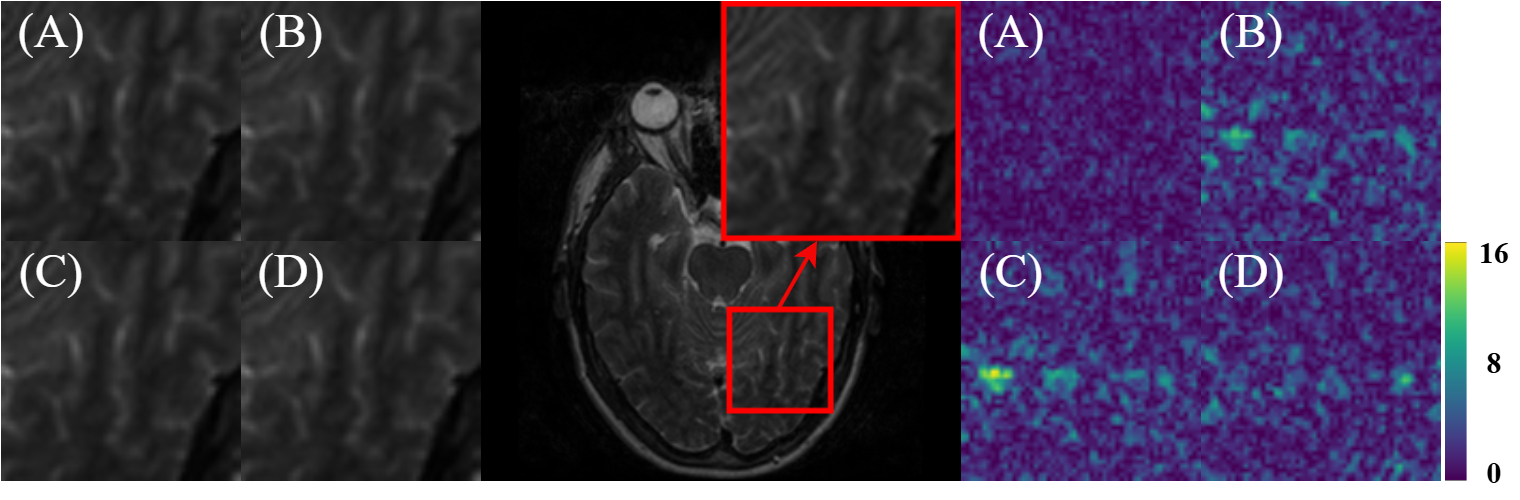

Refer to caption

Figure 6: Visual comparison of different methods on the IXI dataset. The first row of each group shows the reconstruction result, while the second row indicates the error map. Group (A) uses a 1D random undersampling mask with ×\times4 acceleration rate, while Group (B) uses a ×\times8 rate mask.

IV-D Qualitative Results

Figs. 6, 7, and 8 present qualitative comparisons of these models on IXI, BraTS, and M4raw datasets, respectively. Group (A) corresponds to 1D random undersampling with ×\times4 acceleration rate, while Group (B) corresponds to ×\times8 setting. In addition, the first row of each group shows the reconstruction result, while the second row indicates the error map. Obviously, our MambaMDN achieves superior preservation of structural details and significantly reduces reconstruction errors compared to other methods. The proposed framework consistently maintains high-fidelity texture representation and precise anatomical boundary delineation across varying undersampling rates, exhibiting remarkable robustness and versatile adaptation to different acquisition scenarios.